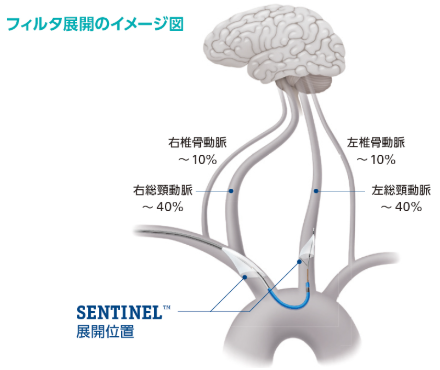

本製品は、TAVI手技中に腕頭動脈と左総頸動脈の入口部に一時的に フィルタを留置することで、脳卒中のリスクとなり得る弁尖や石灰化病変の組織片、心筋筋組織、血栓等の塞栓物質を捕捉、除去します。1つのサイズで留置する動脈の多様な解剖に対応しています 。また、これらの血管は脳への血流の主要経路を担っており、本製品のフィルタにより脳全体への血流の約90%を保護することで、TAVI手技中の塞栓物質による、術後の脳卒中リスクを低減できる可能性があります。